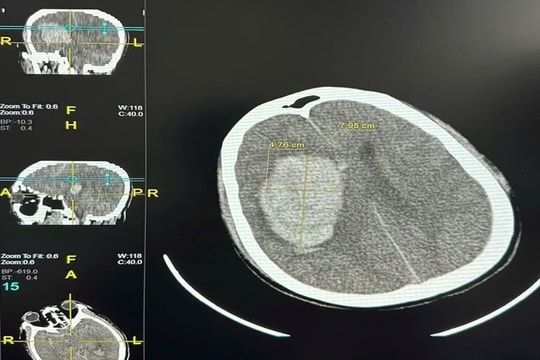

Kết quả chụp cắt lớp vi tính sọ não và dựng mạch cho thấy, bệnh nhân bị chảy máu não lớn hai bên thùy đỉnh do huyết khối xoang tĩnh mạch dọc trên và hội lưu xoang. Xét nghiệm D-Dimer tăng cao vượt ngưỡng 5.000 ng/mL.